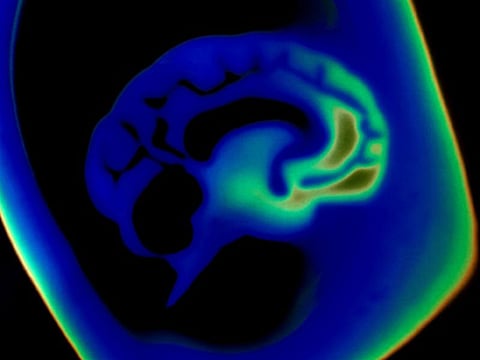

THURSDAY, Jan. 13, 2022 (HealthDay News) -- Real-world use shows the Woven EndoBridge (WEB) device is safe and effective for treating brain aneurysms, according to a research letter published online Dec. 17 in Stroke.

Adam A. Dmytriw, M.D., from Massachusetts General Hospital in Boston, and colleagues presented multicenter data to aid decision-making and prognostication when considering the use of a WEB device. The analysis included both ruptured and unruptured aneurysms (683 in 671 patients) in all intracranial locations treated at 22 academic institutions with the WEB device.

The researchers found that at a median 11 months of follow-up, adequate occlusion was seen for 85.7 percent of aneurysms and complete occlusion occurred in 57.8 percent. No re-ruptures occurred. Overall, 7.8 percent of aneurysms required retreatment and 7.5 percent of procedures had thromboembolic complications, of which 4 percent were symptomatic and 2 percent were permanent. Hemorrhagic complications were documented in 3 percent of procedures. Lower rates of adequate aneurysm occlusion were significantly associated with minor compaction (adjusted odds ratio [aOR], 0.45; 95 percent confidence interval, 0.24 to 0.86; P = 0.015) or major compaction (aOR, 0.25; 95 percent confidence interval, 0.11 to 0.57; P = 0.001) versus no compaction. Immediate remnant aneurysm (aOR, 0.45; 95 percent confidence interval, 0.18 to 1.00; P = 0.065) at the end of procedural digital subtraction angiography was associated with less adequate aneurysm occlusion on last follow-up compared complete occlusion.